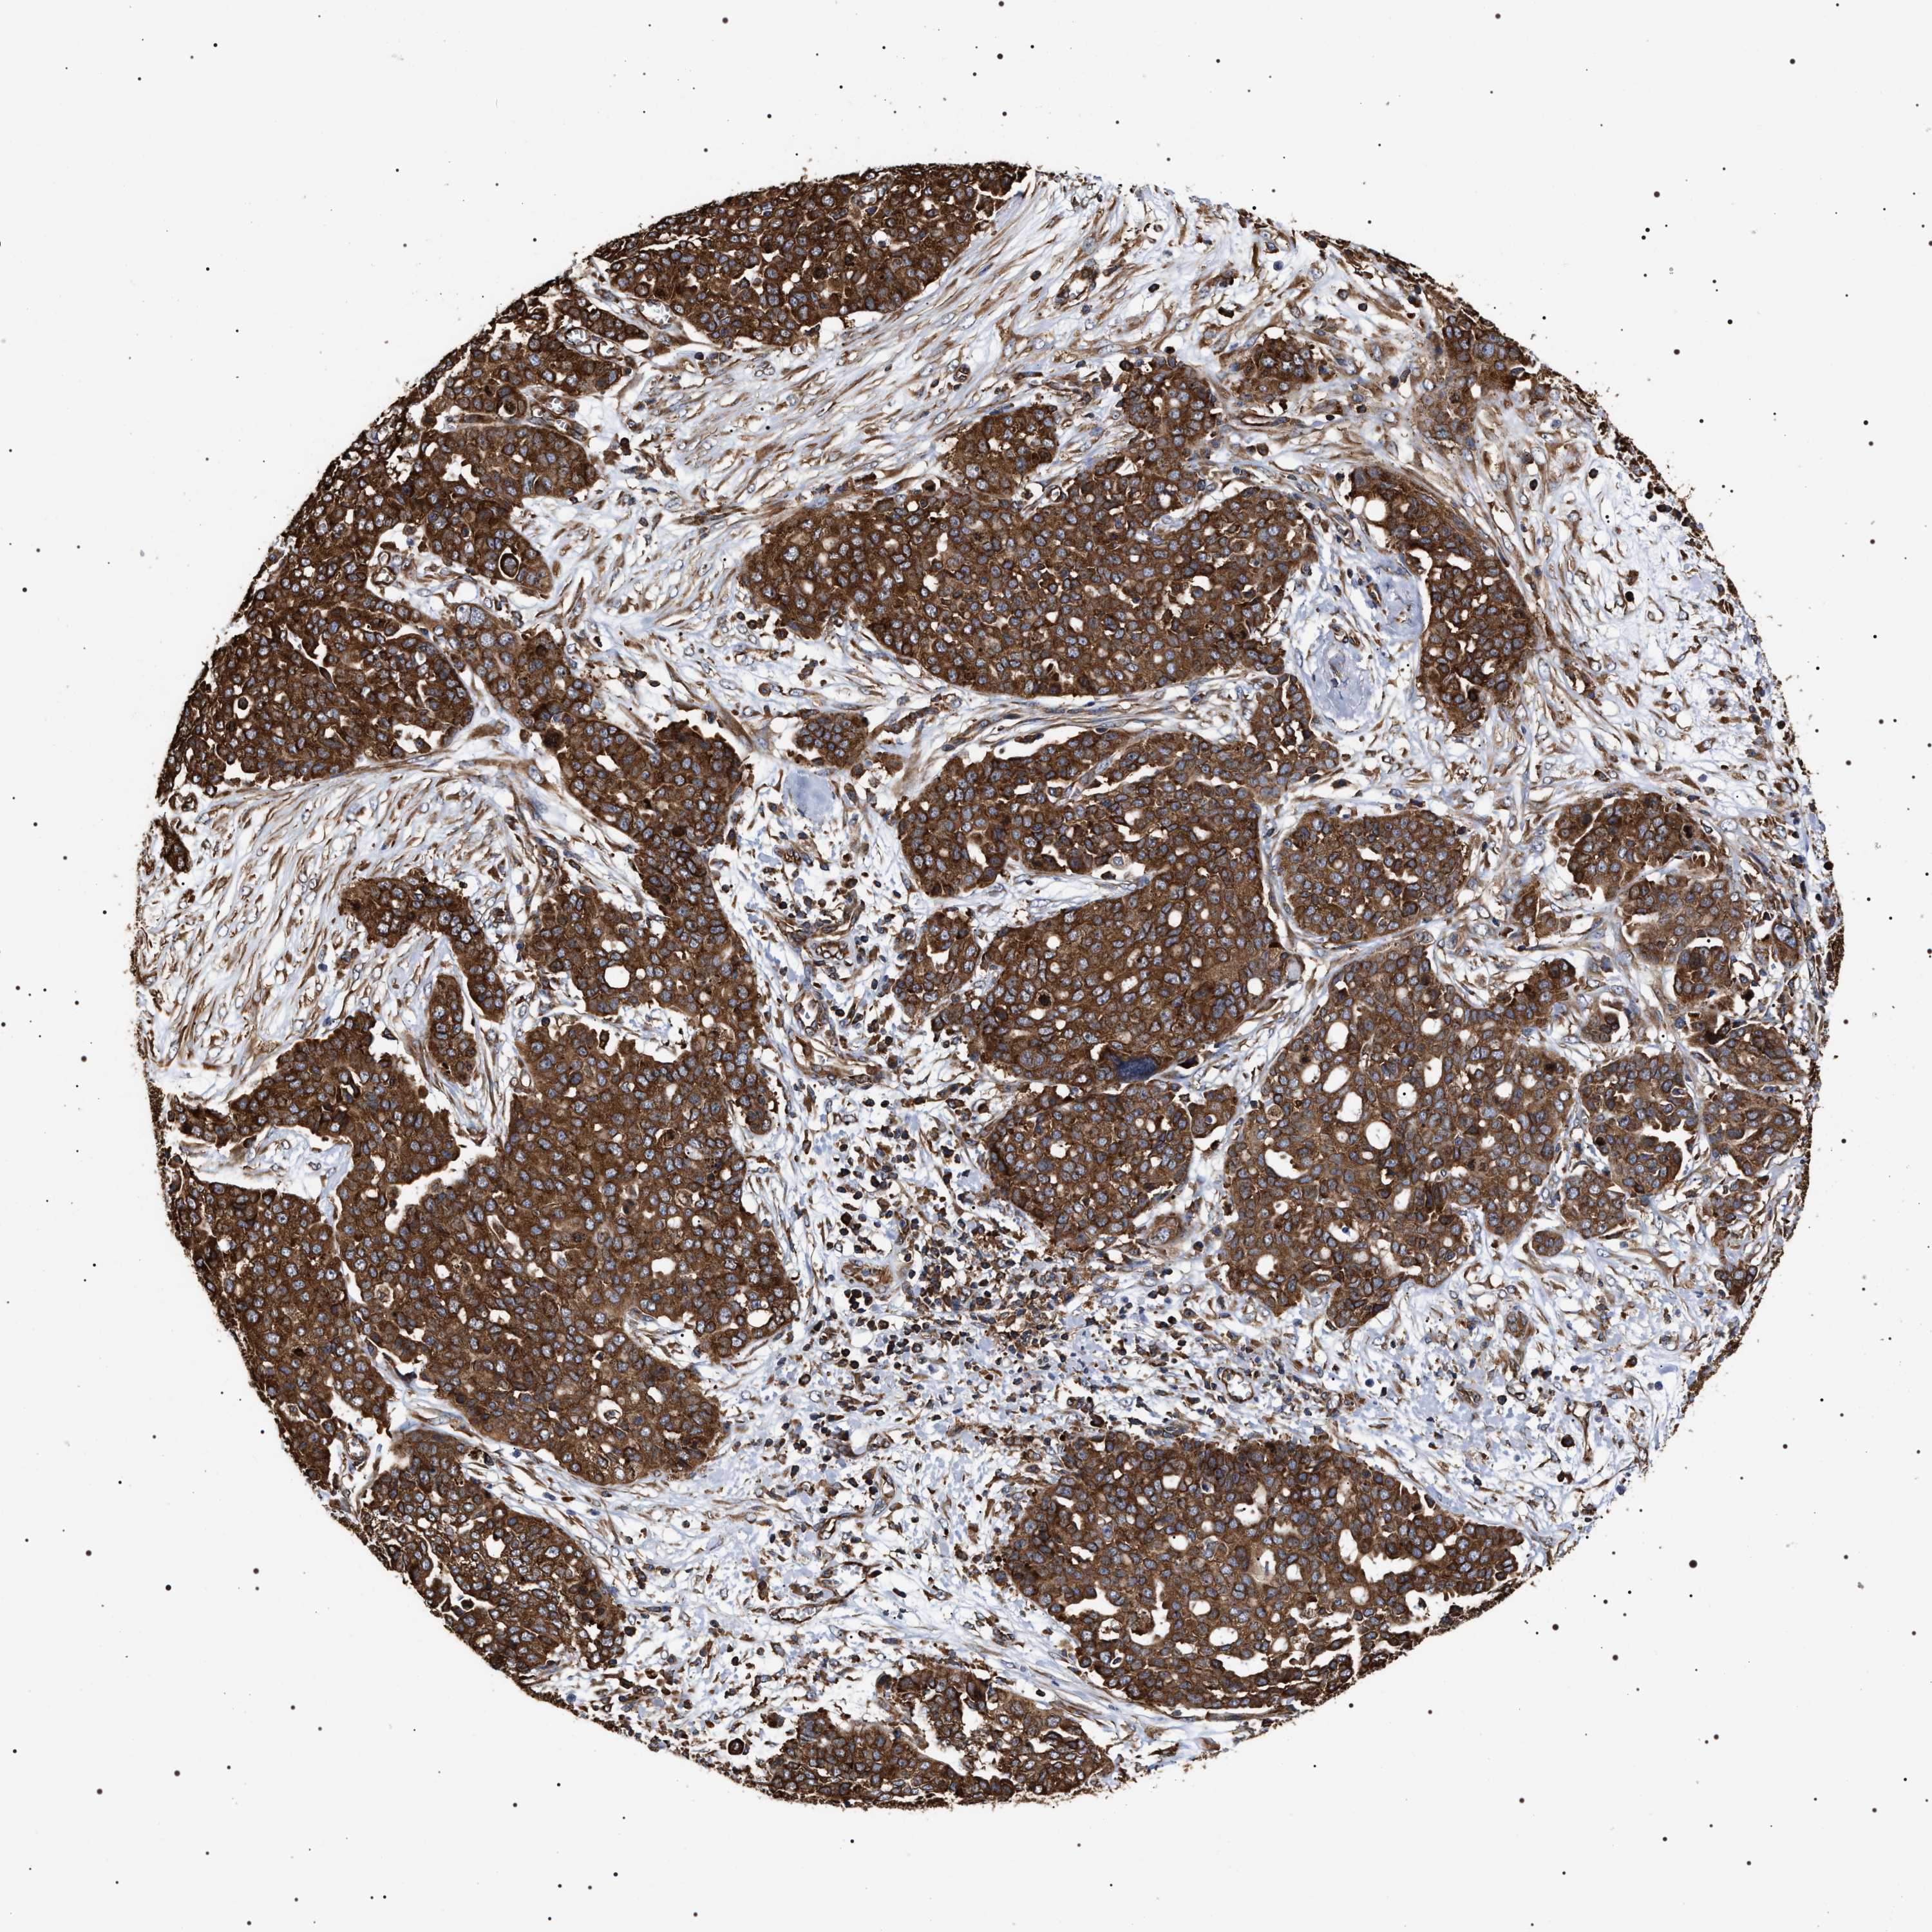

OVARIAN CANCER - Protein expressioni

A mouse-over function shows sample information and annotation data. Click on an image to view it in a full screen mode. Samples can be filtered based on level of antibody staining by selecting one or several of the following categories: high, medium, low and not detected. The assay and annotation is described here.

Note that samples used for immunohistochemistry by the Human Protein Atlas do not correspond to samples in the TCGA dataset.

Antibody stainingi

Antibody staining in the annotated cell types in the current human tissue is reported as not detected, low, medium, or high, based on conventional immunohistochemistry profiling in selected tissues. This score is based on the combination of the staining intensity and fraction of stained cells.

Each image is clickable and will lead to virtual microscopy that enables deeper exploration of all samples and also displays staining intensity scores, fraction scores and subcellular localization as well as patient and tissue information for each sample.

Antibody HPA020559

Antibody CAB026297

Cystadenocarcinoma, serous, NOS

Carcinoma, endometroid

Cystadenocarcinoma, mucinous, NOS

Carcinoma, NOS